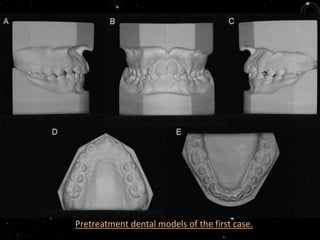

A healthy 11-year-old boy was brought by his parents for orthodontic

treatment in Rio de Janeiro, Brazil. At the initial orthodontic

evaluation he was already in the permanent dentition, with an Angle

Class I malocclusion and a small mandibular arch-length discrepancy

(-1.6 mm). The lateral cephalometric analysis showed a Class I

skeletal malocclusion (ANB, 4)

Pretreatment dental models of the first case.

Protruded maxillary and mandibular incisors (1.NA= 27, 1.NB= 27;

IMPA= 91). The lower left central incisor showed some gingival

recession. The facial profile was convex. There was a tooth

discrepancy with a mandibular excess of 1.7 mm. Total discrepancy

of the lower arch was calculated by adding up the arch-length

discrepancy and the cephalometric discrepancy (-5,6 mm).